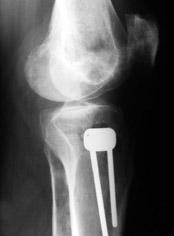

Yesterday one leg was done (my plan to make both in one session were cancelled because of external reasons). So much exciting and useful experience.

The osteotomy line i planned to make a bit oblique, but not so as you suggested. But at the moment of osteoclasis after corticotomy through the anterior stab wound the line became almost as you described. Now problem is how to reproduce thee line at the next leg ;-)

The prominent fragment seems to be useful for cosmetic purposes, because aesthetic guys perform medialization of the distal fragment to gain attractive curve at the medial side of the leg. Also all locking options became available - initially i planned to engage only two most

proximal 45 degree holes.

I cut the fibula because i externally rotated the distal fragment by 6-7 degrees. With only angular correction it didn't show any displacement.

Today CT for estimation of rotation was performed, results i will see only tomorrow. Rotation of the operated limb can be corrected with the second surgery. Comments/critics are welcome.

Снимки в приложении - фас сравнительный с неоперированной ногой. Жду критики.

Впрос про остеотомию большеберцовой непраздный. Эта получилась при надломе несколько более наклонно, чем я делал (сейчас проблема,

как на второй ноге сделать так же). Вот этот высоящий "зуб" центрального отломка не заменит ли в плане косметики то, что получается при медиализации дистального?